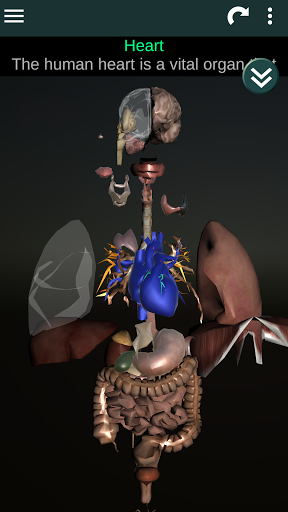

Menampilkan model anatomi 3D dari organ utama tubuh manusia dan penjelasannya masing-masing.

Apa yang ada di aplikasi?

* Sistem pencernaan, termasuk lambung, usus kecil, usus besar, dan animasi sistem ini.

* Sistem pernafasan, yang meliputi trakea, bronkus, paru-paru dan animasi sistem ini.

* Otak, yang meliputi otak, otak kecil, dan batang otak.

* Jantung, yang meliputi atrium, ventrikel, aorta, dan animasi organ ini.

* Mudah diakses dan dinavigasi (zoom, rotasi 3D).

* Deskripsi masing-masing organ.